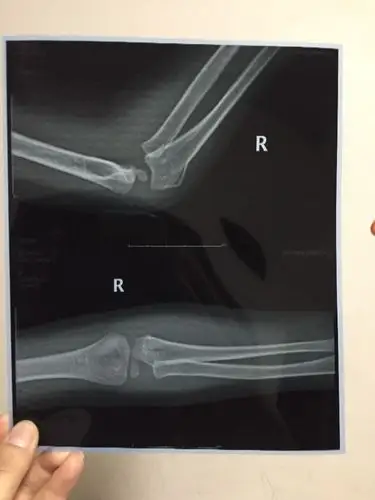

台州男子酒驾被查逃跑时把交警手臂弄骨折了

19个月手臂骨折 [病例帖]